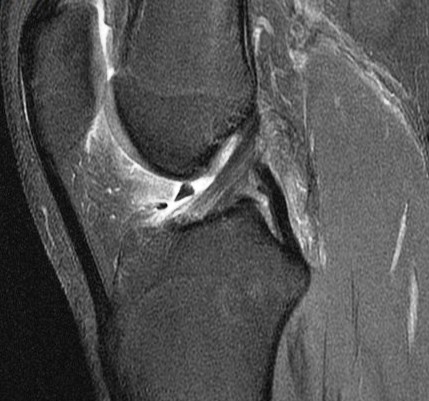

15 y/o F soccer injury lateral pain. r/o lateral meniscus.

Figure 2 for case Unstable displaced lateral meniscus flap tear( RID2763 )

Figure 2

The flap is folded and displaced into the notch.

Unstable displaced lateral meniscus flap tear( RID2763 )